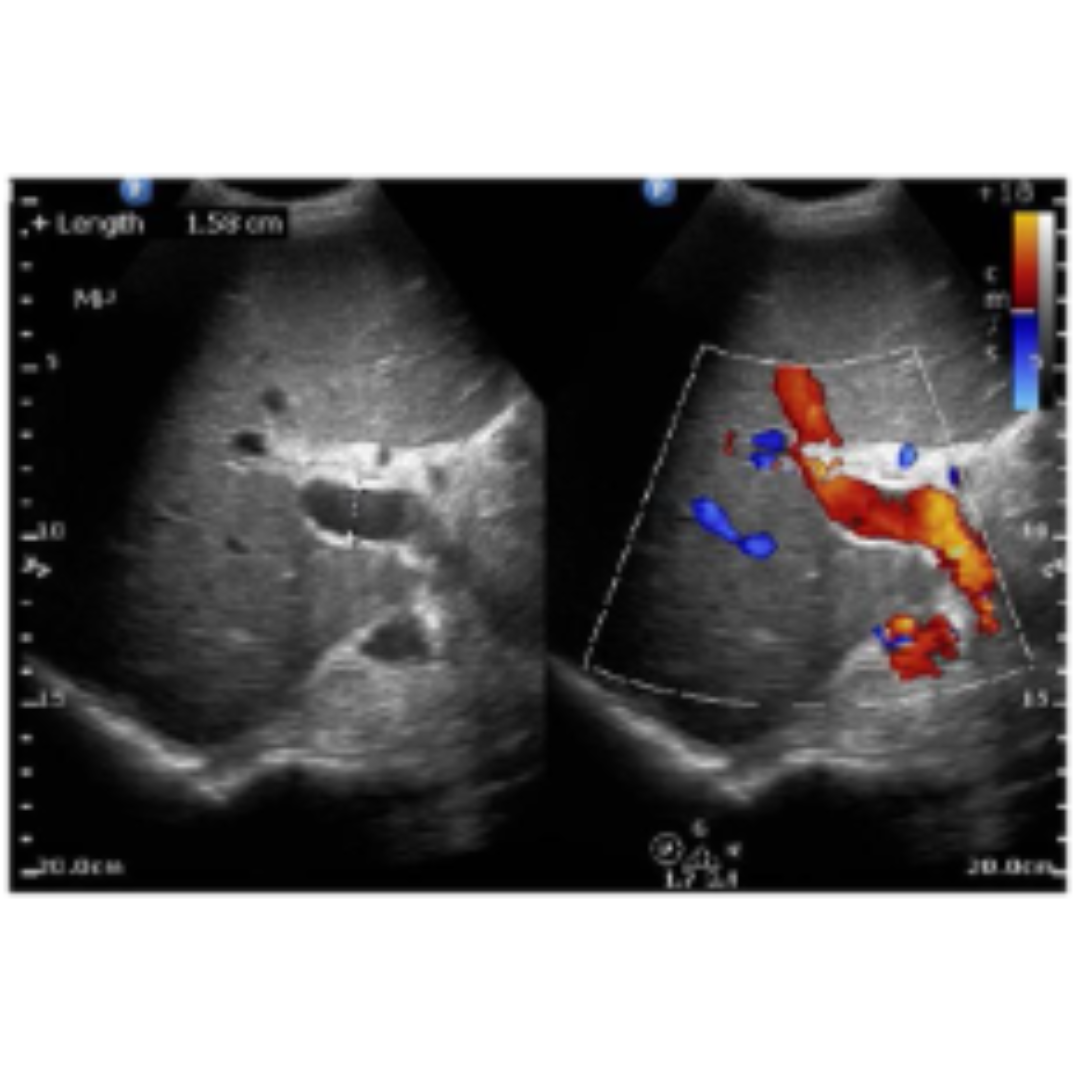

• Hipertensión portal (diámetro AP > 13 mm)

• Velocidad de vena porta ≤ 16 cm/sg

Figura 6: Aumento del diámetro de la porta.